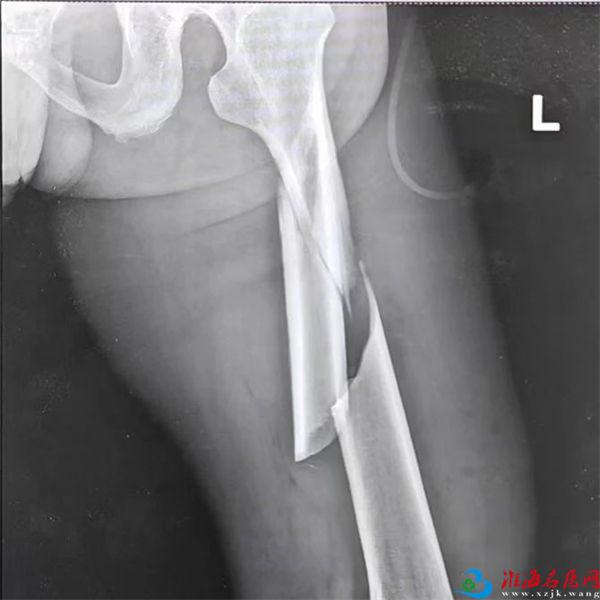

X线检查显示:双侧股骨干粉碎性骨折。

看到胶片上碎裂的股骨影像,孙先生的心沉入谷底,骨头碎成这样,自己还能站起来吗?